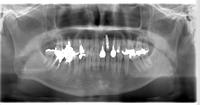

上顎臼歯部のソケットリフトによる骨造成をおこなった症例

上顎臼歯部のソケットリフトによる骨造成をおこなった症例をご紹介します。

K様 30代 女性

上顎の奥歯の方の骨がなく、ソケットリフトを用いて骨造成を行い、インプラントを埋入しました。

術前レントゲン写真です。

インプラント埋入直後のレントゲン写真です。

↑上のレントゲンを見ると、ドーム状に膨らんでいるのがわかります。

被せ物装着した後のレントゲン写真です。

↑最初薄かったレントゲン像が、周囲の骨と一体化し骨化したのがわかります。